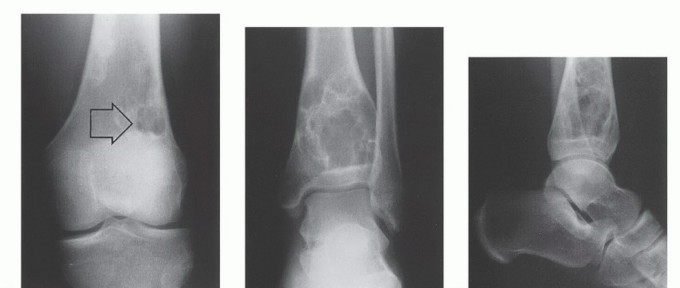

- Plain Radiography: The cornerstone of initial evaluation. It accurately predicts the diagnosis in over 80% of extremity bone tumors. It defines the lesion's location, zone of transition (narrow/sclerotic = benign/slow; wide/permeative = malignant/aggressive), cortical destruction, and periosteal reactions (Codman triangle, onion-skinning, sunburst pattern).

- Computed Tomography (CT): The modality of choice for assessing fine osseous detail, cortical integrity, and matrix mineralization. Thin-slice (≤1 mm) helical CT allows for precise 3D reconstructions. Intravenous contrast is essential to delineate the relationship of the soft tissue mass to major vascular bundles. Chest CT is mandatory for staging to rule out pulmonary metastases.

- Magnetic Resonance Imaging (MRI): The gold standard for evaluating the local extent of the tumor. It accurately defines the intramedullary extent (allowing calculation of bone resection levels), soft tissue extension, joint involvement, and the presence of skip metastases. T1-weighted images best define marrow replacement; T2-weighted and STIR sequences highlight peritumoral edema and the soft tissue mass. Contrast enhancement differentiates cystic from solid components and clarifies neurovascular proximity.

Enneking also established a robust staging system for benign osseous lesions based on clinical presentation and radiographic behavior:

* Stage 1 (Latent): Asymptomatic, discovered incidentally. Static growth or spontaneous healing. Thick, well-defined reactive sclerotic rim. Treated with observation or simple curettage (e.g., Non-ossifying fibroma).

* Stage 2 (Active): Progressive growth, mild symptoms, but contained within natural cortical barriers. Treated with extended curettage and burr drilling (e.g., Aneurysmal bone cyst).

* Stage 3 (Aggressive): Rapid growth, symptomatic, destroys cortical bone, and extends into soft tissue. Minimal to no reactive bone rim. Requires aggressive extended curettage with local adjuvants (liquid nitrogen, phenol, argon beam) or wide en bloc resection (e.g., Giant cell tumor of bone).